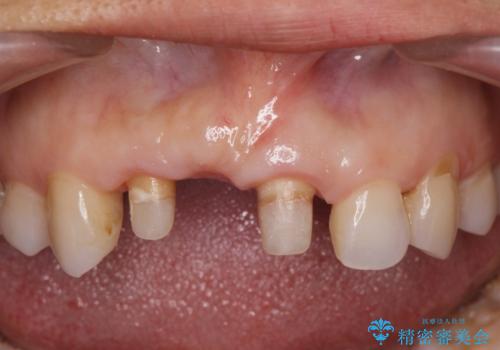

- 前歯のブリッジがすぐに外れる、歯ぐきが腫れている、見た目を良くしたい、と希望され来院されました。

現在装着されているブリッジを除去したところ、歯ぐきよりも上に存在する歯質(縁上歯質)が少なく、土台の形態の悪さや不適合などさまざまな問題があります。